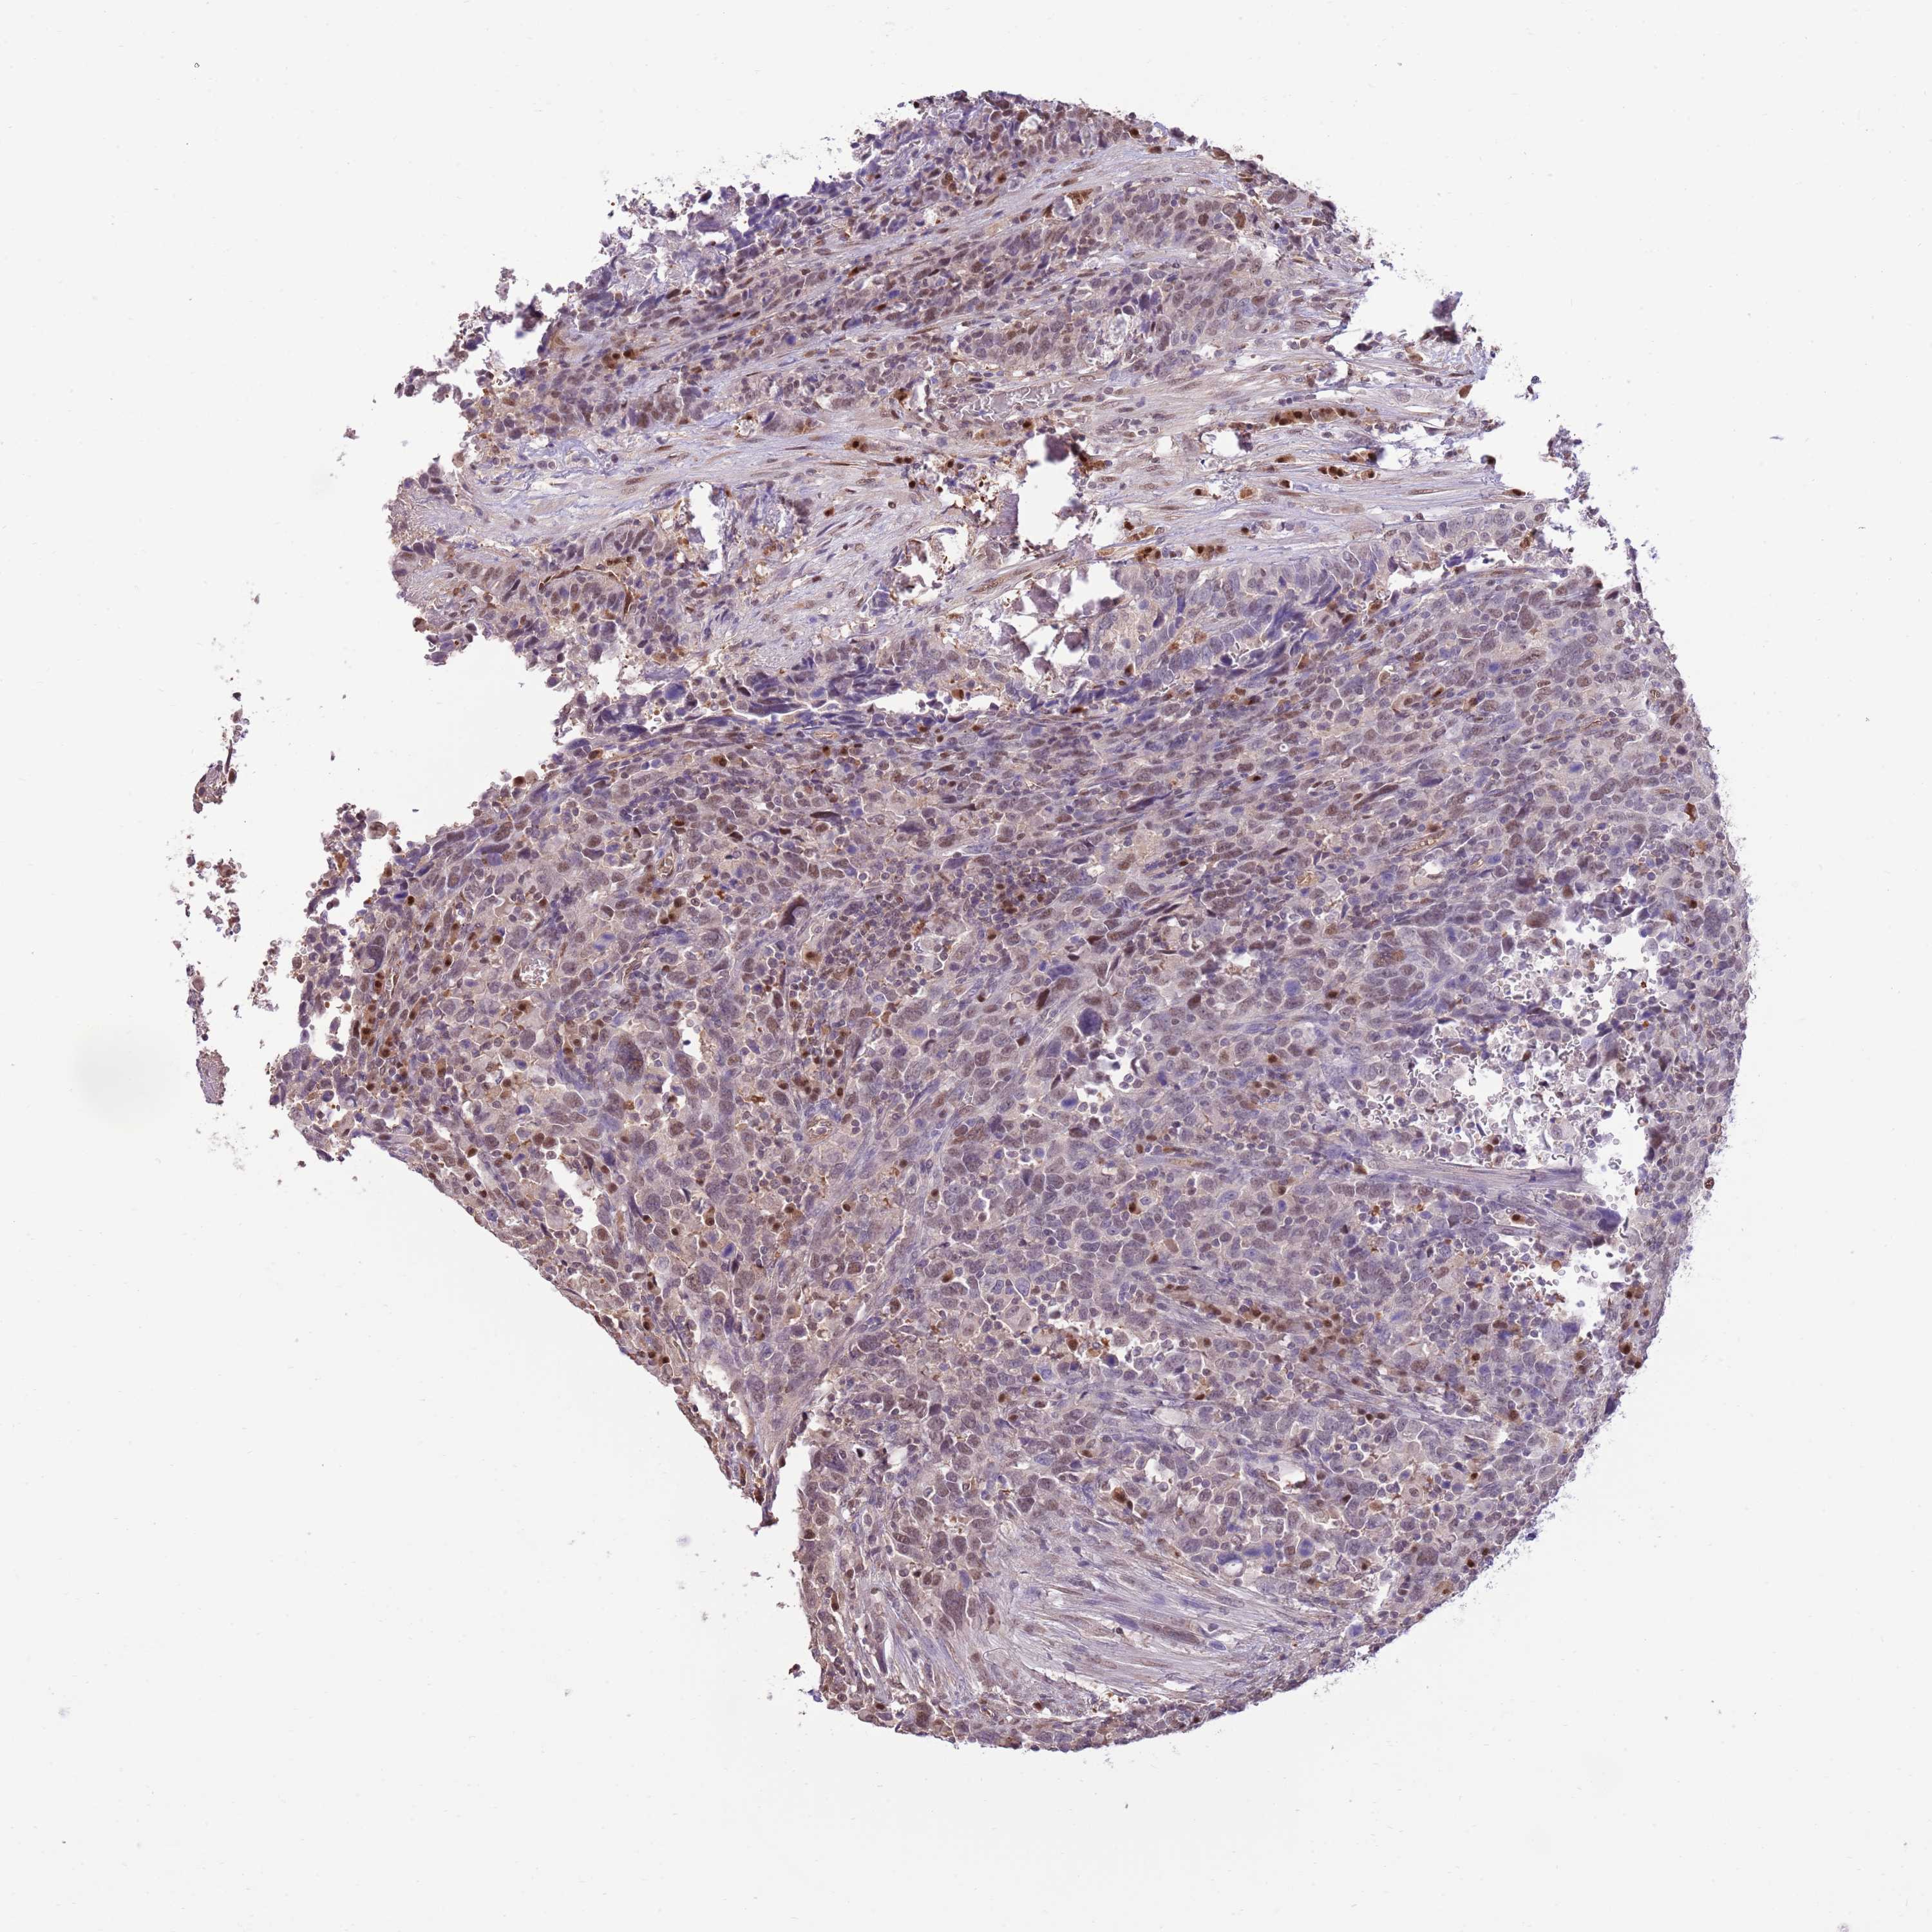

UROTHELIAL CANCER - Protein expressioni

A mouse-over function shows sample information and annotation data. Click on an image to view it in a full screen mode. Samples can be filtered based on level of antibody staining by selecting one or several of the following categories: high, medium, low and not detected. The assay and annotation is described here.

Antibody stainingi

Antibody staining in the annotated cell types in the current human tissue is reported as not detected, low, medium, or high, based on conventional immunohistochemistry profiling in selected tissues. This score is based on the combination of the staining intensity and fraction of stained cells.

Each image is clickable and will lead to virtual microscopy that enables deeper exploration of all samples and also displays staining intensity scores, fraction scores and subcellular localization as well as patient and tissue information for each sample.

Antibody HPA047108

Antibody HPA050628

Staining

High

Medium

Low

Not detected

Intensity

Strong

Moderate

Weak

Negative

Quantity

>75%

75%-25%

<25%

None

Location

Nuclear

Cytoplasmic/membranous

Cytoplasmic/membranous,nuclear

Urothelial carcinoma, Low grade

Urothelial carcinoma, High grade

Urothelial carcinoma, NOS